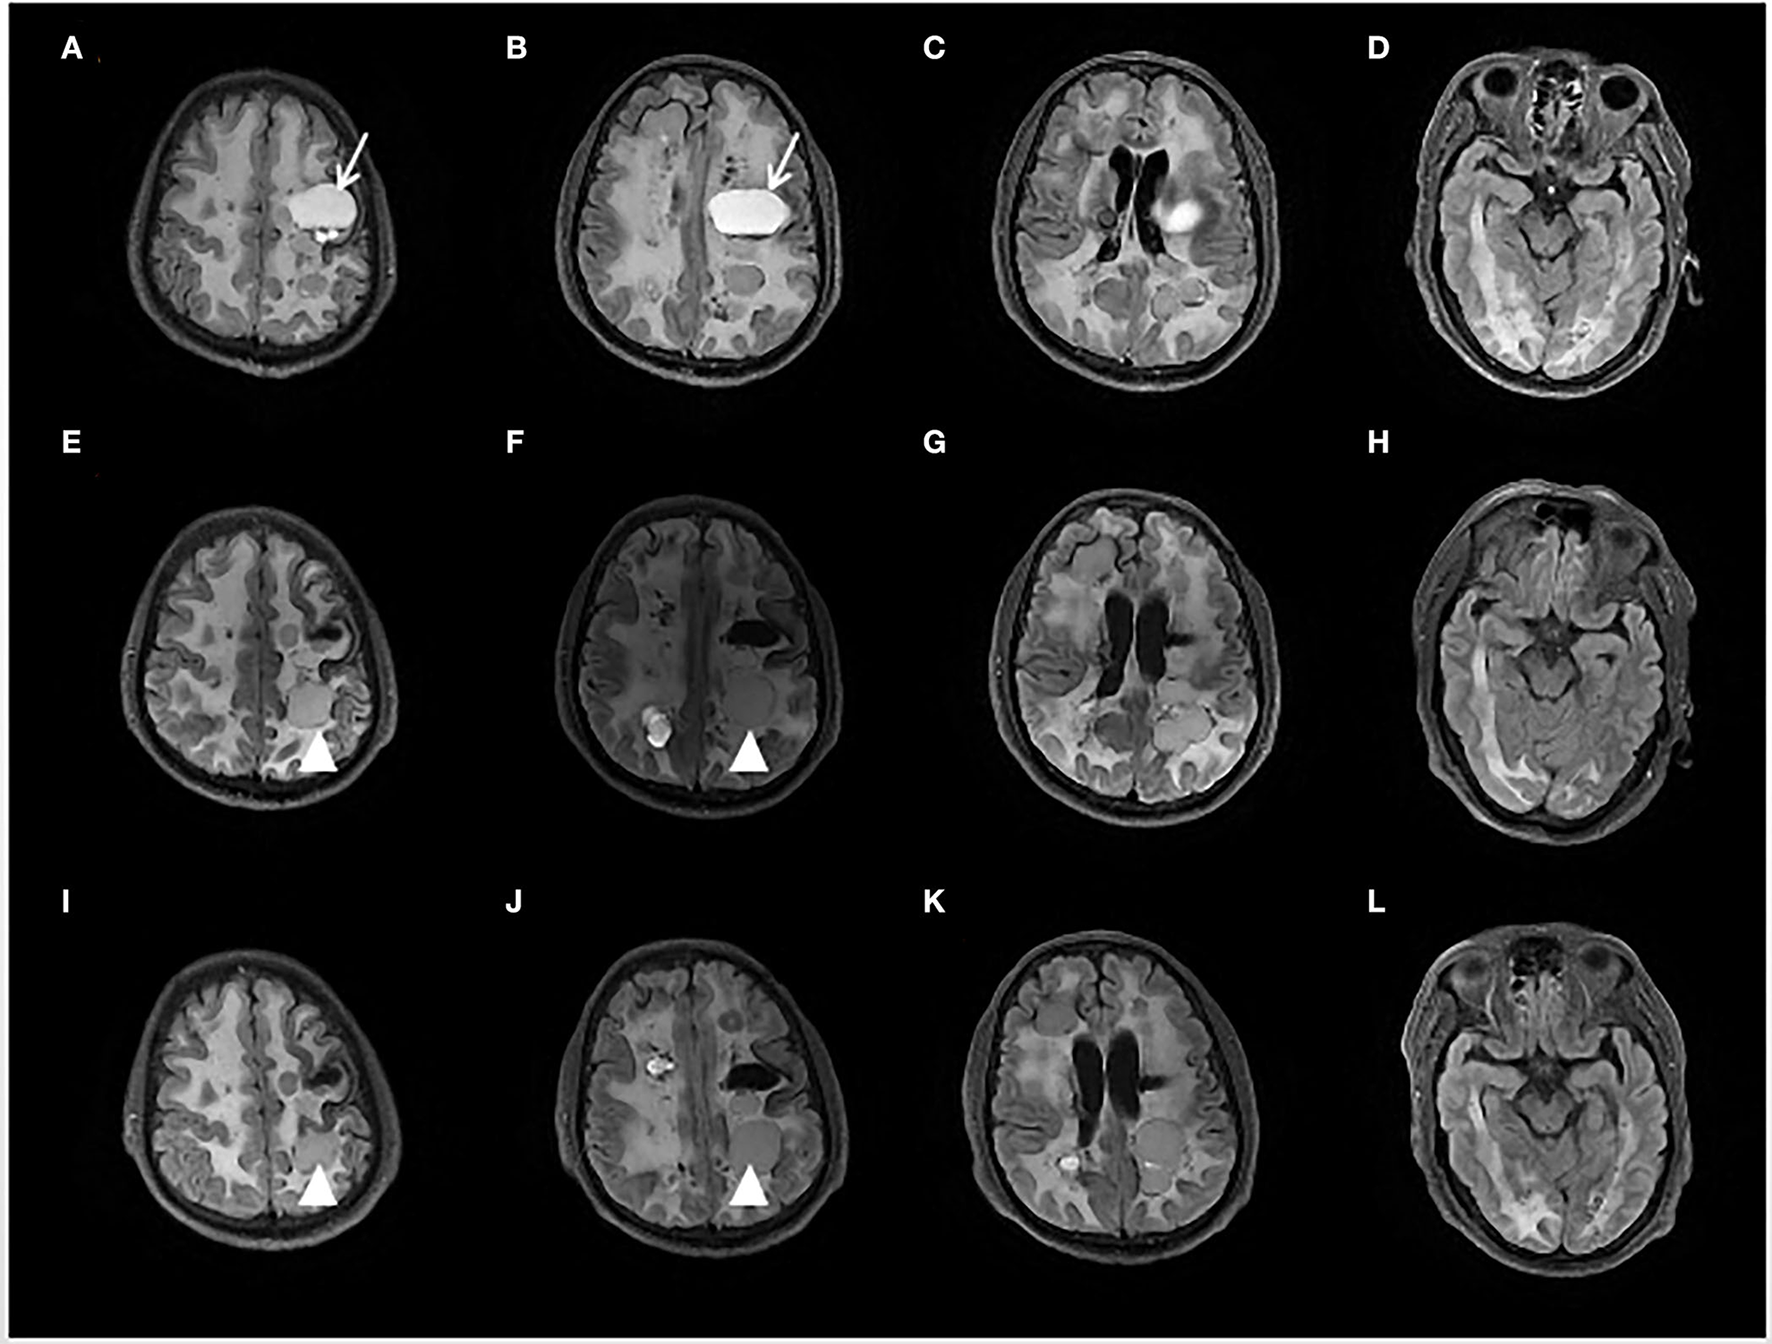

A 53-year-old man had his first episode of generalized tonic-clonic seizure in November 2017. Two months later, he developed jerks restricted to the right limb followed by transient weakness. At a local hospital, a brain MRI showed diffuse hyperintensity in periventricular and deep white matter, and numerous cystic lesions in different sizes in bilateral hemispheres with occupying effects were observed in some images (see Figure 1). The susceptibility-weighted imaging (SWI) and CT indicated wide-spreading remote bleeding and calcification. He was given sodium valproate 0.5 g twice a day and levetiracetam 0.5 g twice a day, and seizure frequency stabilized to 2–4 times each year. Due to progressive cognition decline and persistent weakness of the right limb, he was admitted for diagnostic evaluation and management in October 2020.

Brain fluid-attenuated inversion recovery (FLAIR) sequence of initial presentation (A–D), 6 months (E–H), and 12 months (I–L) after Bevacizumab treatment. The initial MRI showed multiple cystic foci and white matter lesions in bilateral cerebral hemispheres. The left mass cystic foci [showed as an arrow in (A,B)] was decompressed by an Ommaya reservoir. After 6 months treatment of Bevacizumab, another left frontal lobe cystic foci [showed as an arrowhead in (E,F,I,J)] was slightly enlarged.

From a radiological perspective, compared with the brain MRI before the trial, the MRI scans at the 6th month and at the 12th month showed minimal changes except for slight enlargement in one cyst (see Figure 1).